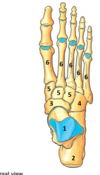

1

body of talus

98

2

calcaneus

99

3

navicular

100

4

cuboid

101

5

medial, intermediate and lateral cuneiform

102

6

metatarsalsv1-5

what joint does inversion and eversion occur at?

talonavicular joint - synovial ball and socket talocalcaneal - synovial plane

1st metatarsal

121

medial cuneiform

122

123

talus

124